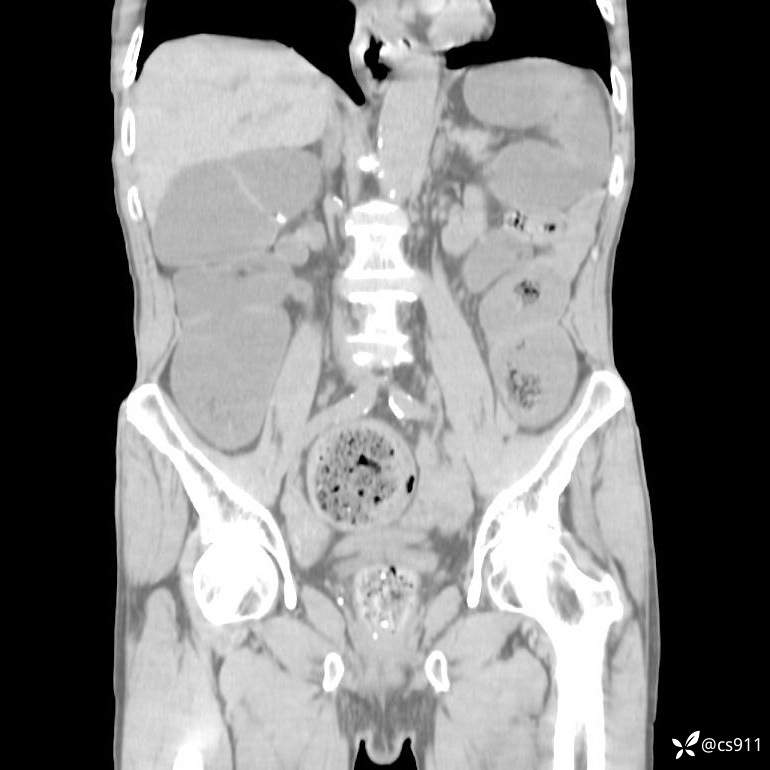

急腹症之急诊CT,原因?答案公布

男,77岁,腹痛、腹胀伴恶心呕吐1天。呕吐胃内容物,非喷射性呕吐,有咖啡色样胃内容物,诉有胃穿孔病史。查体:全腹平,下腹部压痛,全腹无反跳痛,叩诊呈浊音,移动性浊音阴性,肠鸣音减弱,1-2次/分。肛检:直肠未扪及明显肿物,可触及大量粪块。

T 36.6℃ P 80次/分 R 26次/分 BP 100/60mmHg

白细胞(WBC) H 14.55 10e9/L 4-10

中性粒细胞百分率(NEUT%) H 85.7 % 40-75

血淀粉酶(AMY) HH 1859 U/L 35-135

癌胚抗原(CEA) H 27.44 ng/ml 0-5

呕吐物 潜血试验 * 阳性 阴性

患者轮椅入室检查神志清楚, 能配合摆位和呼吸